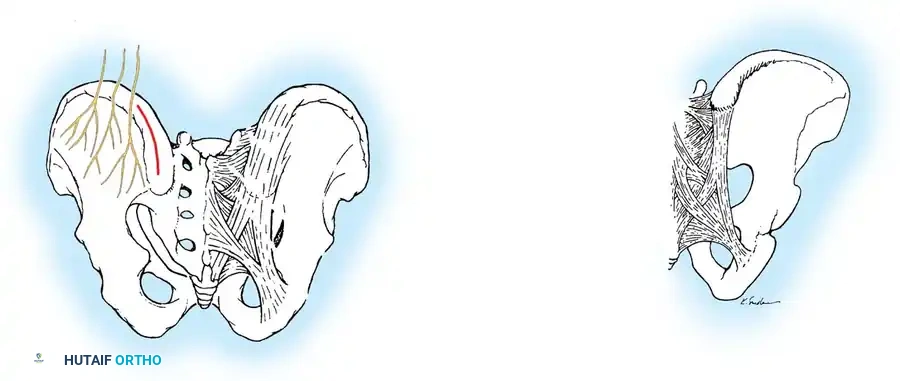

Lateral Exposure and Hemostasis

- Transverse Process Exposure: Extend the subperiosteal dissection laterally, first exposing the facet joints, and then continuing out to the tips of the transverse processes bilaterally.

- Segmental Vessels: As you dissect lateral to the facet joints, you will encounter the posterior branches of the segmental vessels. These must be meticulously identified and coagulated with bipolar or monopolar cautery to prevent insidious bleeding.

Fig. 38-24: Posterior view of segmental vessels located just lateral to each facet joint, requiring meticulous coagulation.

- Facet Cleaning: Use a sharp curet and a pituitary rongeur to completely excise the facet capsules and clean the interspinous ligaments.